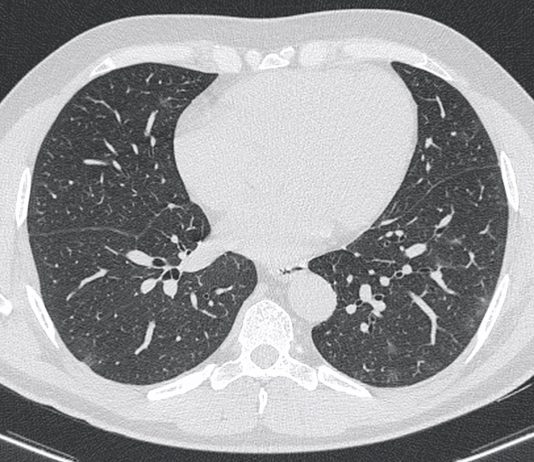

Paziente maschio di 77 anni portato in PS dopo peggioramento clinico (difficoltà ad alimentarsi ed idratarsi) per diarrea, vomito ed epigastralgia da 15 gg. Il paziente condivide abitazione con soggetto...